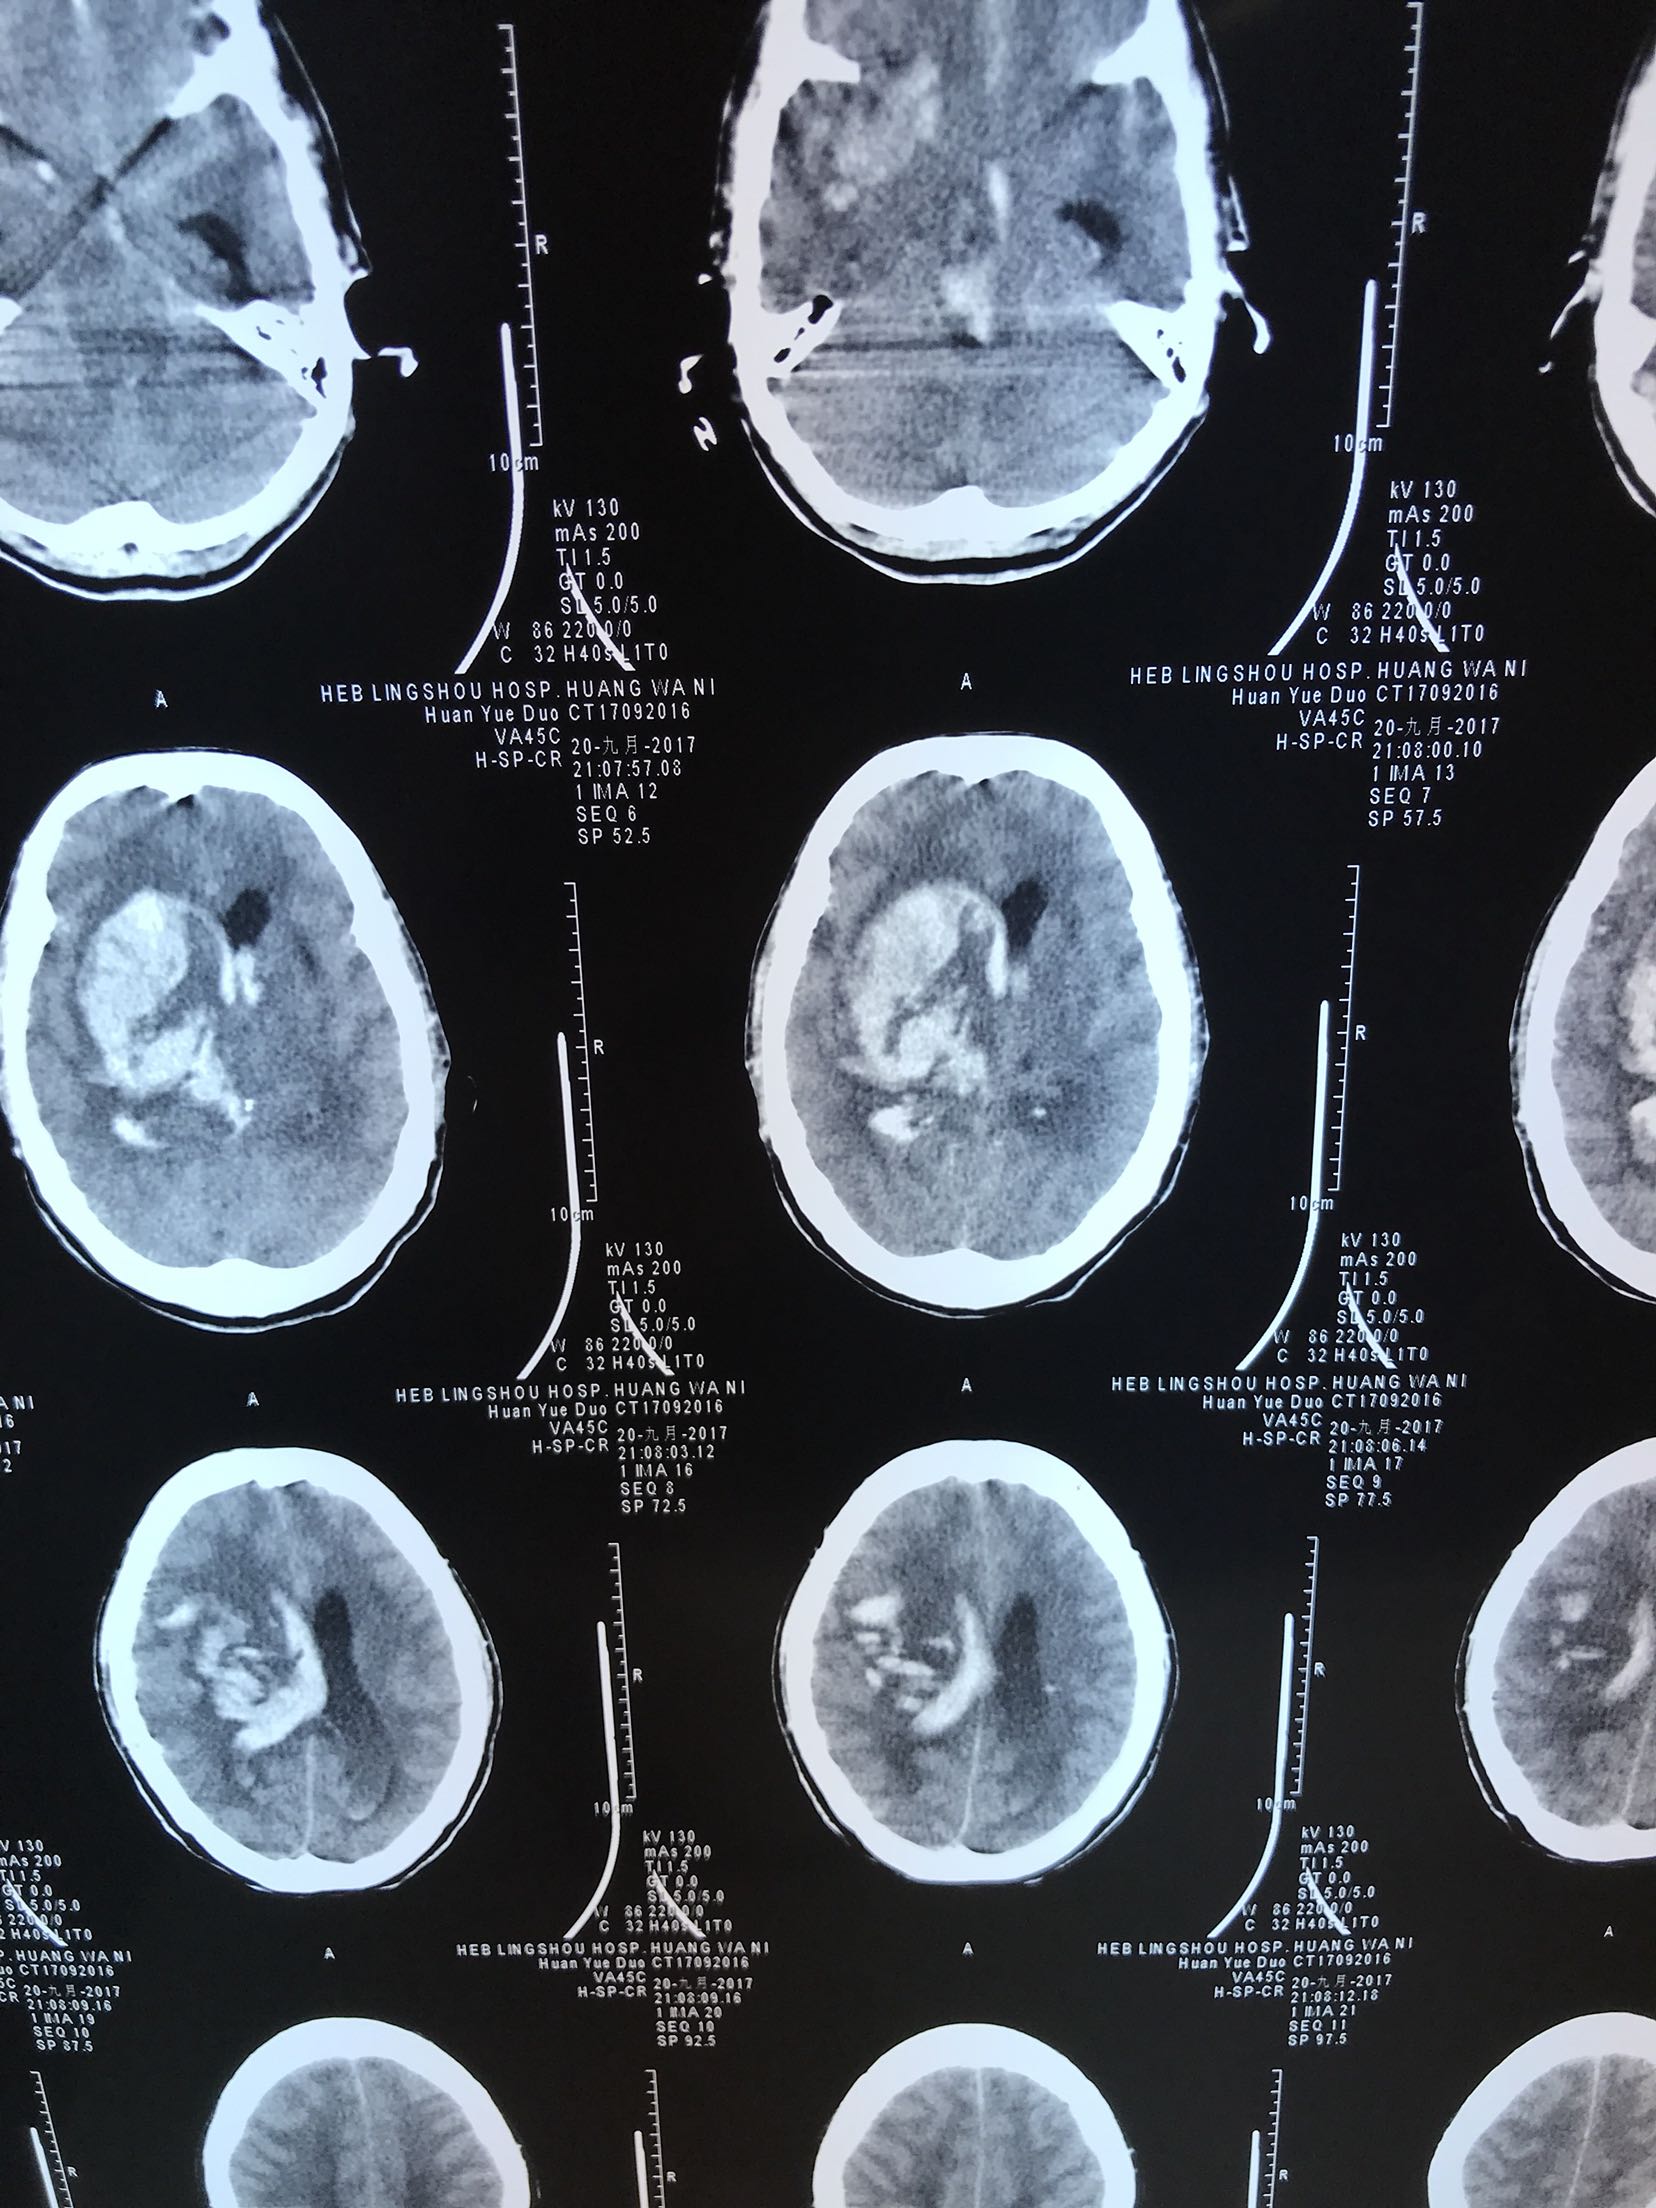

突发意识不清2小时,既往高血压,未口服过药物2小时前患者突发意识不清,急诊急查头CT:右侧基底节丘脑出血破入脑室,脑疝,为进一步治疗收住院

体温35.9℃ 脉搏50次/分 血压180/110mmhg,意识模糊,双侧瞳孔正大等圆,对光反射灵敏,双肺呼吸音粗,未闻及干湿性啰音,心音有力各瓣膜听诊区未闻及杂音,腹软肝脾未触及,肠鸣音正常,双下肢无水肿,四肢肌力不清,双侧巴氏征阳性

大面积脑出血 脑疝 高血压3级 极高危,家属拒绝手术,给于保护脑神经,脱水降颅压等治疗

患者经治疗2天,仍意识不清,血压低,去甲肾上腺素维持血压。